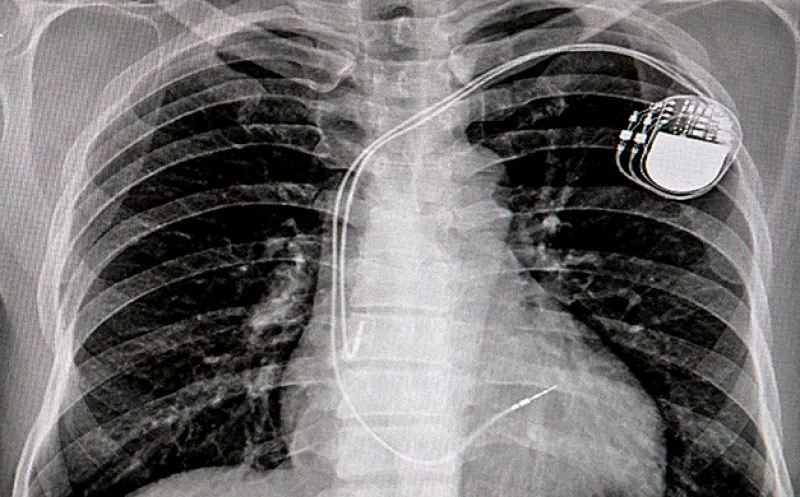

Doctorul a implantat dispozitive cardiace unor pacienți care nu aveau nevoie de o astfel de intervenție

Procurorii îl mai acuză pe medicul Tesloianu că a introdus dispozitive cardiace implantabile, inclusiv extrase de la pacienți decedați, unor pacienți care nu aveau nevoie de astfel de astfel de intervenții.

Cardiologul realiza acest lucru consemnând un diagnostic fictiv – bradicardie – care să justifice necesitatea prescrierii unui stimulator cardiac sau prescriind medicamente care să provoace reacții de natură a conduce la simptomatologia specifică, „ignorând riscul de a provoca pacienților probleme medicale grave sau chiar decesul”. În fapt, manifestările clinice ale pacienților sunt asociate bradicardiei medicamentoase, ca urmare a planurilor de tratament administrate la recomandările sale anterioare, premeditate și care ar fi putut fi remediate prin schimbarea medicamentației.